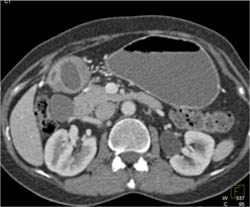

Antral Carcinoma